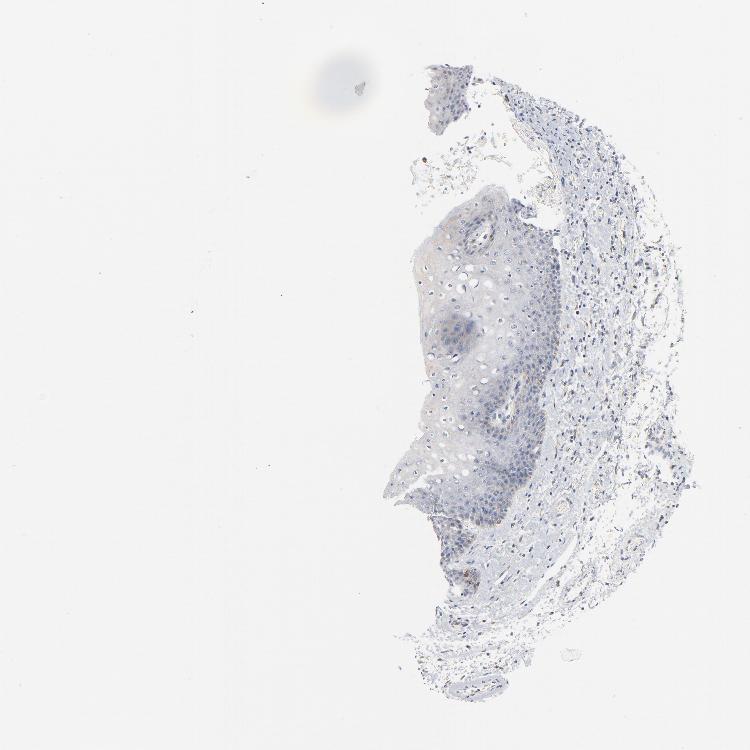

SKIN 1 - Antibody stainingi

Antibody staining in the annotated cell types in the current human tissue is reported as not detected, low, medium, or high, based on conventional immunohistochemistry profiling in selected tissues. This score is based on the combination of the staining intensity and fraction of stained cells.

Each image is clickable and will lead to virtual microscopy that enables deeper exploration of all samples and also displays staining intensity scores, fraction scores and subcellular localization as well as patient and tissue information for each sample.

Antibody HPA003438

Langerhans Not detected

Fibroblasts Not detected

Keratinocytes Not detected

Melanocytes Not detected

SKIN 2 - Antibody stainingi

Epidermal cells Low